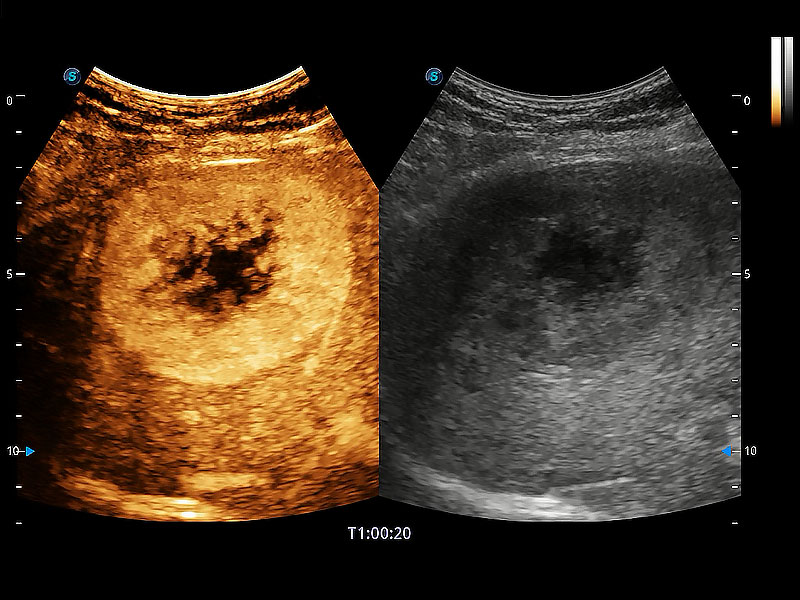

极大提升超低速微细血流的检出能力,同时更精准地滤除软组织和超声信号,为兽用医生提供以往无法通过常规血流获得的疾病诊断信息。

在传统二维血流成像的基础上,呈现血流的立体感,具有动感的生命力之美。即便是微小的血管也能轻松应对,提高了血流的视觉敏感性。

非线性融合造影成像充分利用谐波和基波信号,为难以观察的血流进行增强显像。可用于线阵、凸阵、微凸阵、相控阵探头。